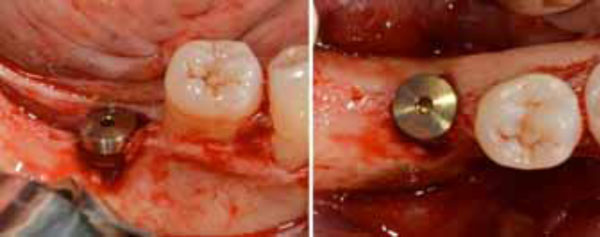

Positioned dental implant with a cower screw on it in frontal (a) and occlusal (b) views.

Second surgery showing the membrane retrieval (a) and the uneventful healing of the recipient site (b).

Given the severe vertical alveolar bone defect, the implant site was underprepared. An 8 mm long pilot hole was drilled, and a 5 mm wide and 11.5 mm long implant (BT KONIC Implant, Biotec BTK, Italy) was placed (Fig. 5). Its platform on the ideal line was located 2 mm below the cementoenamel junction (CEJ) of the adjacent teeth but 2.5 mm above the alveolar ridge because of the vertical bone defect in the first molar region (Fig. 6). The insertion torque was 70 Ncm, confirming the implant’s good primary stability. The peri-implant bone defect resulting from the alveolar atrophy and underpreparation was filled using a heterologous bone material made of corticocancellous porcine bone particles prehydrated with collagen gel (OsteoBiol mp3, Tecnoss Dental, Italy).